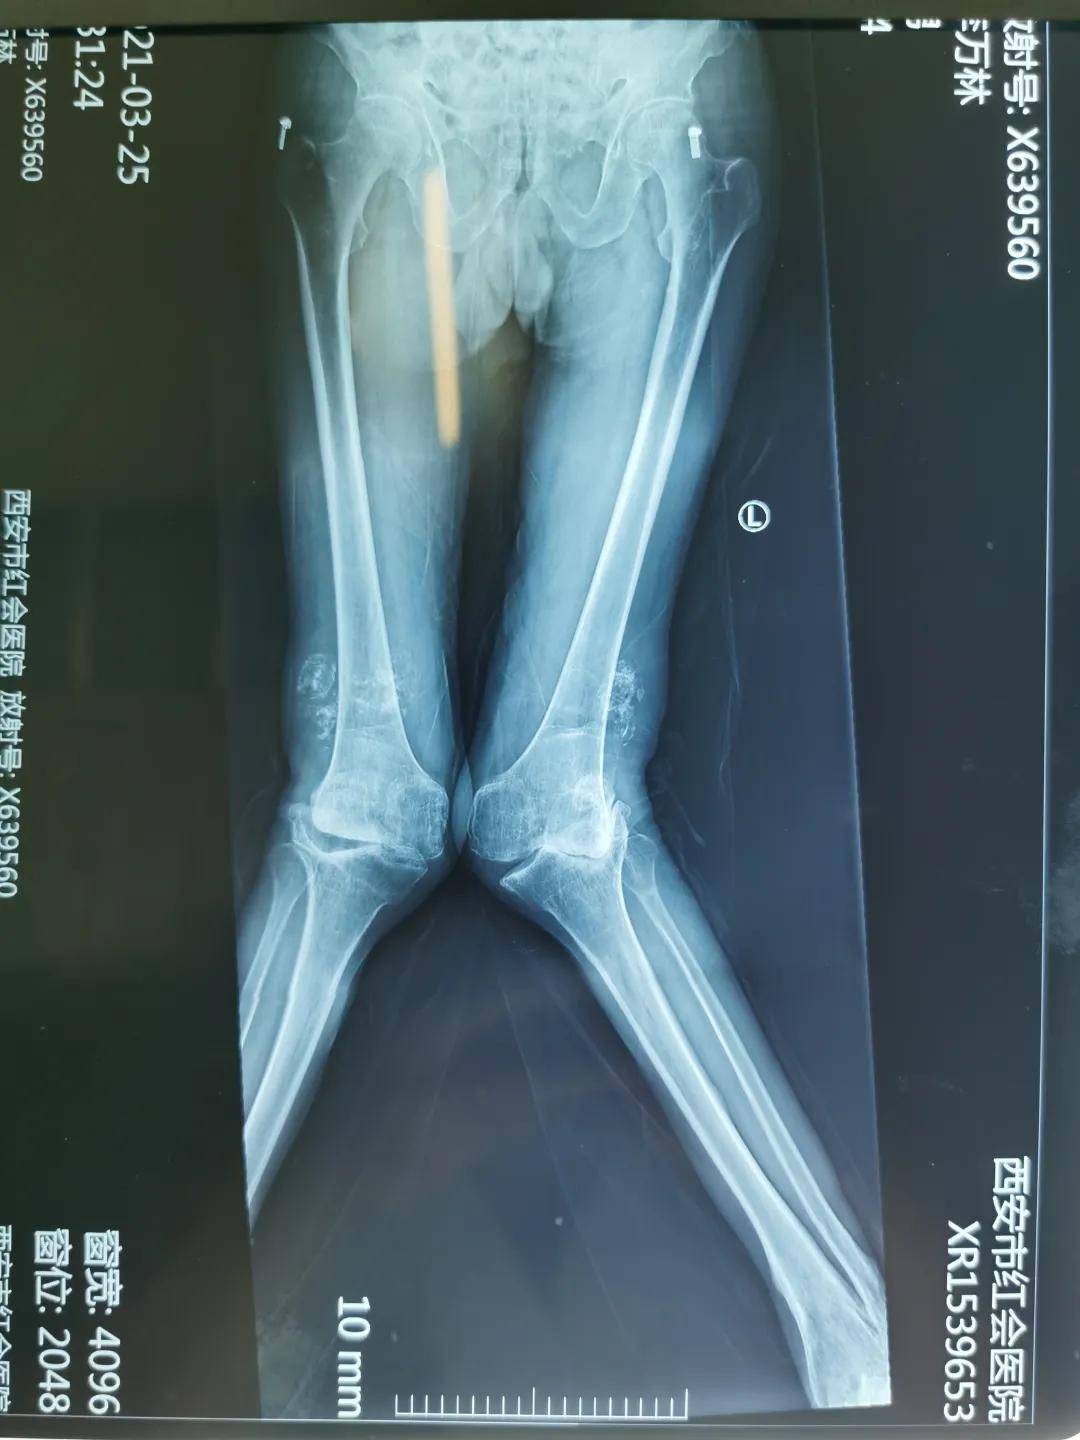

患者李某 , 男 , 64岁 , 甘肃省某县人 , 以“大骨节病”收治入院 。 患者十余年前因大骨结病导致双膝关节严重外翻畸形 , 需长期乘坐轮椅 , 完全丧失独立行走能力 , 辗转多家医院求诊 , 因手术难度大 , 风险高 , 未能得到救治 。

完善各项相关检查后 , 在郭浩院长带领下 , 邀请麻醉科、器械厂家、护士进行学科讨论 , 制定了精细的手术方案 , 由于患者双膝外翻畸形大于30度 , 术前因疼痛完全丧失独立行走能力 , 膝关节外翻畸形的膝关节置换难度大 , 外侧软组织松解困难 , 易出现髌骨脱位 , 神经损伤等并发症 。 在充分完成各项准备后 , 于2021年4月在全麻下行“右侧人工全膝关节置换术” , 术中生命体征平稳 , 手术历时2小时 , 顺利结束 , 患者恢复良好 , 术后第三天便在助步器保护下下地活动 。